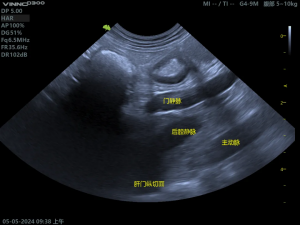

(1)正常肝脏影像

(2)胆囊粘液囊肿影像

胆囊内呈现“猕猴桃征”或“星芒状”的回声。胆囊壁增厚、胆泥淤积、可评估胆囊是否破裂。